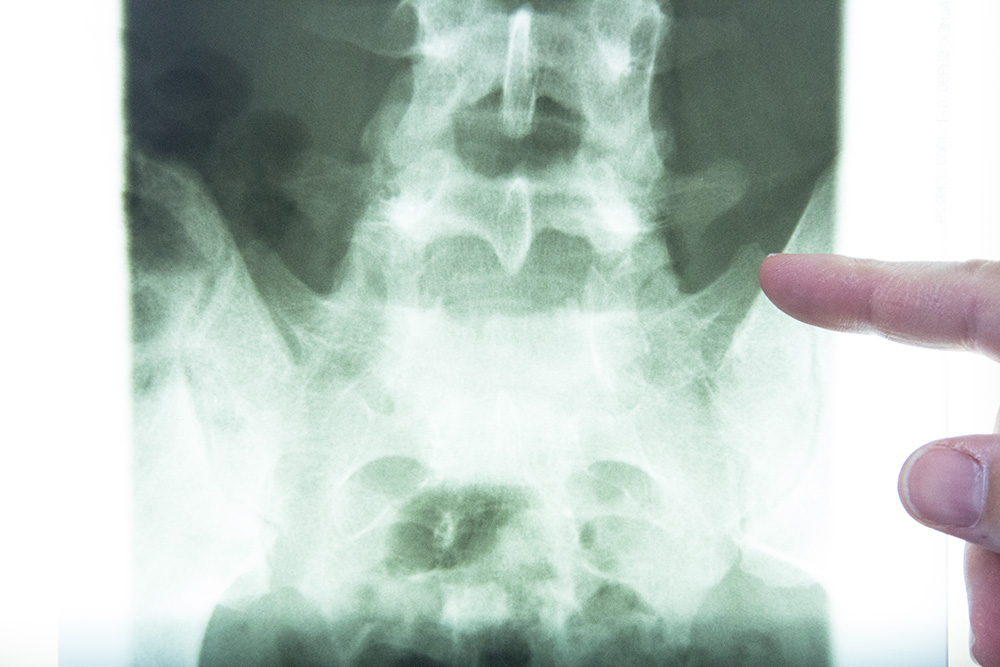

- Knochendichtemessung zur Erkennung einer Osteoporose

- DXA-Messung an der Lendenwirbelsäule und den Schenkelhälsen der Hüftgelenke

Knochendichtemessung (Osteodensitometrie)

Aufgaben der Knochendichtemessung sind die Überprüfung, ob eine Osteoporose nach der Definition der WHO (World Health Organisation) vorliegt und / oder die Kriterien einer belegten Wirksamkeit einer medikamentösen Therapie erfüllt werden Zusätzlich wird das Ausmaß der Knochendichteerniedrigung erfaßt. Daraus leitet sich das individuelle Knochenbruchrisiko die Empfehlungen der therapeutischen Maßnahmen ab.

Wir bieten das empfohlene Standardverfahren zur Knochendichtemessung die Osteodensitometrie mittels der "Dual-X-Ray-Absorptiometrie" (DXA) an der Lendenwirbelsäule und am proximalen Femur an.